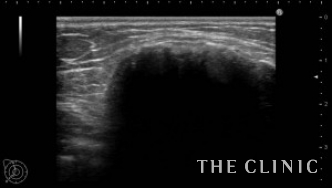

10年前に脂肪注入を受けられ、大きなしこりが出来たとのことで当院へご相談にご来院されました。触診では右に5㎝、左に6㎝の硬いしこりを触知し、エコーでは乳腺下に石灰化したしこりを認めました。